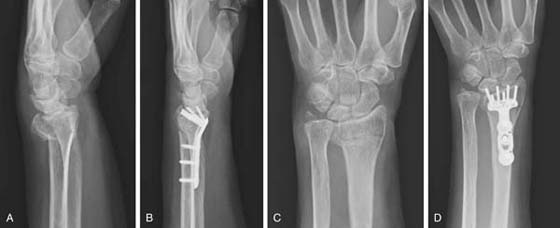

images

Figure 70-26 Radiographs of volar fixed-angle plate for a distal radius fracture. A, Lateral view of distal radius fracture. B, Lateral view of volar plate. C, Anteroposterior view of distal radius fracture. D, Anteroposterior view of volar plate. (Courtesy of Michael Nancollas, MD, Orthopedic Associates of Central New York, Syracuse, New York.)